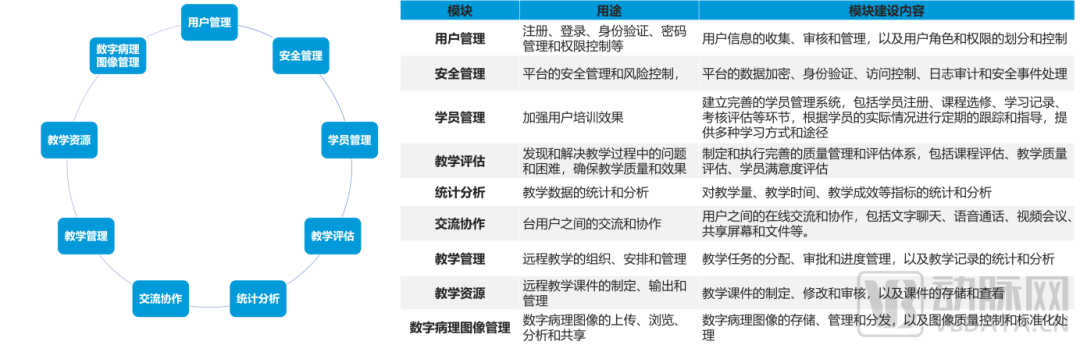

数字化病理科建设模块介绍

数字化建设模块图